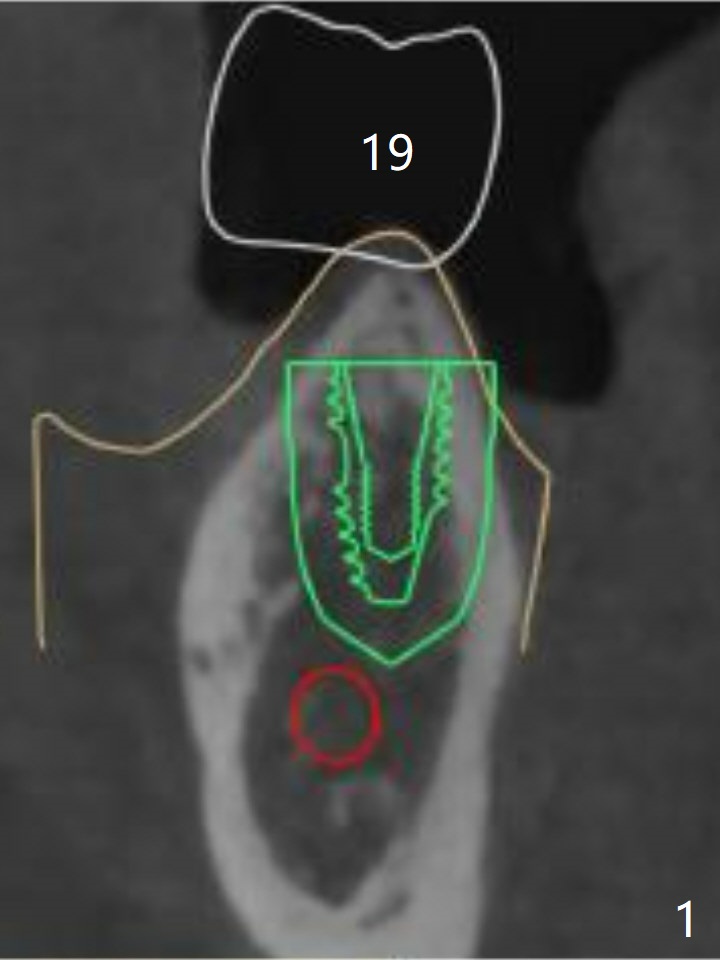

Bone Trimmer Cannot Cut Crestal Bone at #19

According to design, a 5x7 mm implant is placed at #18 first, a vertical anchor pin (in fixture) is connected smoothly and osteotomy commences at #19. Following tissue punch, bone trimmer cannot cut the crestal bone. Pointed drill is used without flattening the pointed, hard crestal bone (both cortical and cancellous, Fig.1, as compared to Fig.2 (preop CT coronal section)). It appears that the trajectory of these 2 implant is unaffected by no use of bone trimmer (Fig.3 (red dashed line: the superior border of the Inferior Alveolar Canal)). There is no paresthesia postoperatively. Retrospectively, should the crest be flattened by a surgical bur after tissue punch and removal of the guide? Yes, said Jennifer.